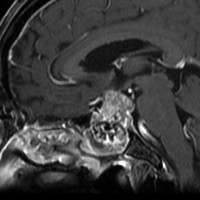

MRI T2強調画像(左)では等信号から高信号のまだらな境界が不明瞭な腫瘍が斜台から左海綿静脈洞内に浸潤しているのがみられます。T1強調ガドリニウム増強では,腫瘍がまだらに増強されています。トルコ鞍から鞍上部に伸び,視交差を侵し第3脳室底まで伸展しています。脊索腫が硬膜内に浸潤して神経組織と癒着することは珍しいことではありません。